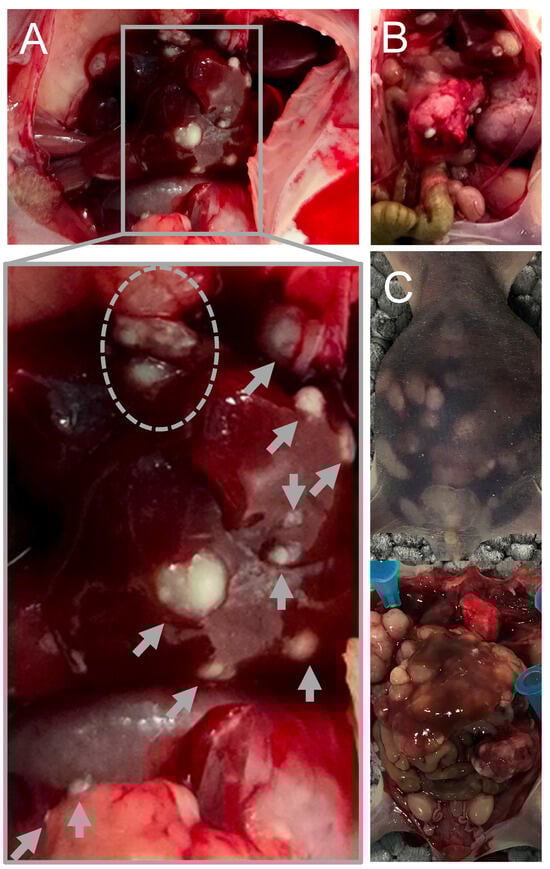

4.1. Establishment of the Mouse Model of Serotonin-Secreting NEN

- Jackson, L.N.; Chen, L.A.; Larson, S.D.; Silva, S.R.; Rychahou, P.G.; Boor, P.J. Development and characterization of a novel in vivo model of carcinoid syndrome. Clin. Cancer Res. 2009, 15, 2747–2755. [Google Scholar] [CrossRef]

- Evers, B.M.; Townsend, C.M.; Upp, J.R.; Allen, E.; Hurlbut, S.C.; Kim, S.W. Establishment and characterization of a human carcinoid in nude mice and effect of various agents on tumor growth. Gastroenterology 1991, 101, 303–311. [Google Scholar] [CrossRef]